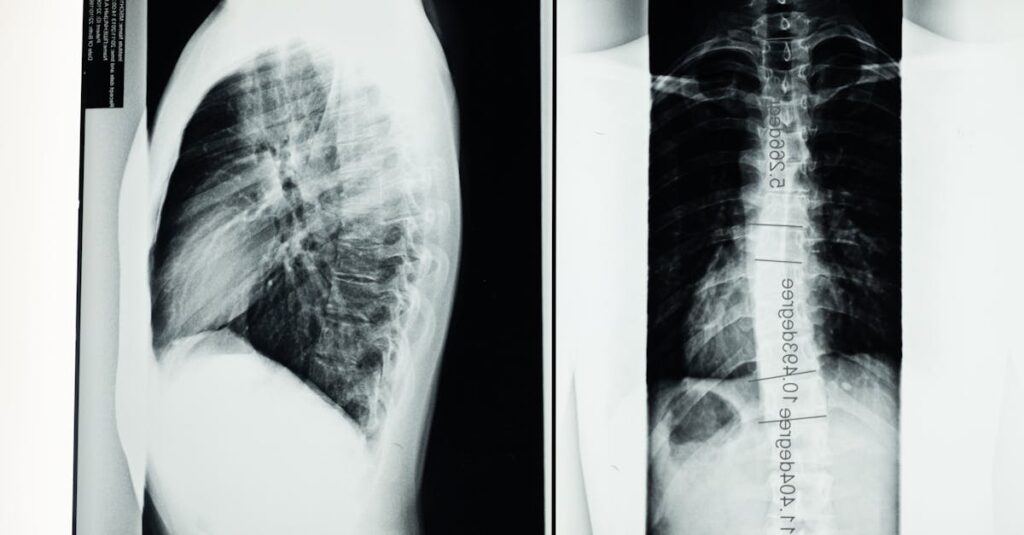

La décompression spinale peut être bénéfique pour de nombreuses conditions liées à la colonne vertébrale. Elle est couramment utilisée pour traiter la sténose spinale, les douleurs chroniques, ainsi que les hernies discales. Chaque cas est unique, et un diagnostic détaillé est essentiel pour déterminer l’approche thérapeutique adéquate.

La décompression spinale repose sur le principe d’appliquer des forces de traction spécifiques sur la colonne vertébrale. En créant un espace entre les vertèbres, cette technique permet de diminuer la pression sur les nerfs et les disques endommagés. Cela intervient particulièrement dans le cas de pathologies comme l’herniediscale ou la sténose spinale, où la pression sur les nerfs peut générer de vives douleurs. En favorisant un meilleur équilibre vertébral, non seulement le patient ressent une diminution de la douleur, mais il bénéficie également d’une meilleure mobilité.

La décompression spinale est particulièrement bénéfique pour les individus souffrant de problèmes vertébraux comme les hernies discales, la sténose spinale, ou les douleurs lombaires chroniques. Cependant, les personnes souffrant d’autres douleurs neuropathiques peuvent également trouver un relâchement grâce à cette technique. Une évaluation préalable par un professionnel de santé est essentielle pour déterminer si cette méthode est adaptée à chaque patient.